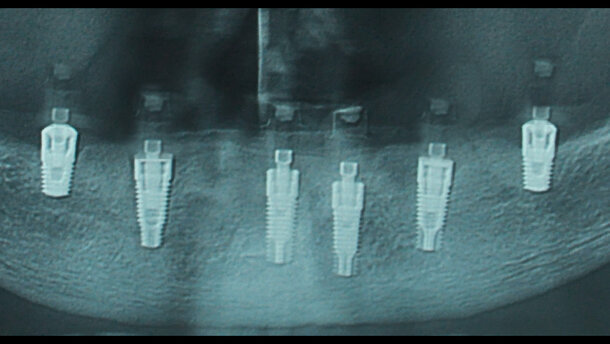

La paziente viene sottoposta a bonifica totale dell’arcata inferiore e contestuale inserimento di 6 impianti endossei: 4 way Milano (Geass, Pozzuolo del Friuli, UD) di diametro 4,5 e lunghezza 11 mm in regione intrasinfisaria e 2 impianti Geass way Short diametro 4,5 piattaforma 4,8 lunghezza 6,5 mm in regione 36 e 46. Il torque di inserimento implantare dei 6 impianti va dai 40 ai 50 Ncm.

Si inseriscono le viti di guarigione sugli impianti, si esegue una ortopantomografia postoperatoria che evidenzia il corretto inserimento implantare (Fig. 2) e si congeda la paziente con terapia farmacologica antibatterica antibiotica sistemica (amoxicillina 0,875, a.clavulanico 0,125) e locale (clorexidina coll. 0,2% e gel), antidolorifica (naprossene) e gastroprotettiva (esomeprazolo).